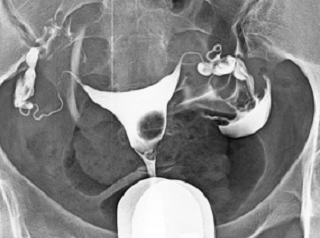

What does HSG assess?

Shape of the uterus

Normal shape

Unicornuate uterus

Complete septate uterus

Patency of fallopian tubes

Open tube

Closed tube

Uterine cavity

Clear/Normal

Submucosal fibroid

Adhesions/Synechiae